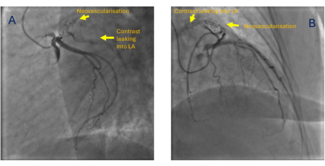

Shivam Arora, MD; Neha Chopra, MD, DM; Shitij Chaudhary, MD, DM

A 50-year-old woman presented to our center with the complaints of breathlessness on exertion for the last 2 years. On evaluation, she was diagnosed with rheumatic heart disease with severe calcific mitral stenosis.

11/20/2025